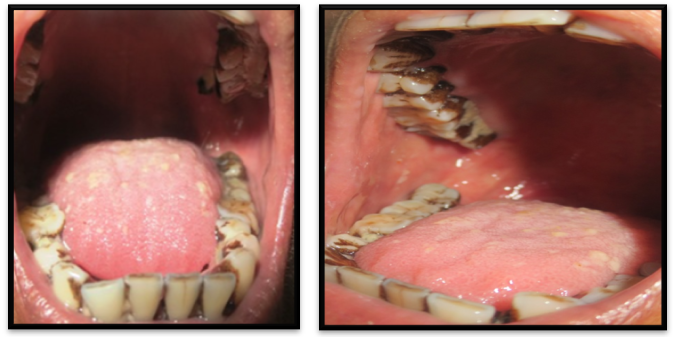

A 65-year-old female patient visited the Department of Oral Medicine and Radiology with the chief complaint of itching and burning sensation in her mouth since one and a half month. Burning sensation increased on taking spicy food. A medical history revealed that she was hypertensive and was asthmatic since 7years. She was treated for asthma with bronchodilator (Salbutamol with Ipratropium bromide) as a reliever. Because of increased frequencies of asthmatic exacerbations her physician prescribed (ICS beclomethasone 400μg) which the patient was using for about 3months. On intraoral examination, diffuse curdy white patches were seen on her tongue, right and left buccal vestibules and mucosa, as well as on her hard palate and soft palatal region with diffuse erythema over the soft palate, uvula, and, with scrapable white patches (Figures 1 & 2). .The complete blood examination & Randam blood Sugar report showed normal reports. On histopathological evaluation, the smear was made from scrapings of these lesions from the palate and tongues separately and sent to the department of Oral Pathology & Microbiology. For cytological evaluation, KOH Staining and H&E staining were done which shows fungal elements. Culture Candida using a Sabouraud's dextrose agar was also done to aid the definitive identification of the fungal organism. Histopathological report confirms the diagnosis as pseudomembranous candidiasis. Patient was advised for CANDID mouth paint twice a day for 15days. And patient was recalled after 15days. So, there was a complete remission of the lesion on the day of call.

Figure 1 Shows the erythematous region in the palate.

Figure 2 Shows curdy white coat on the tongue.

To rule out any underlying systemic cause’s complete hemogram and rapid test for HIV was done which revealed all values within the normal range and nonreactive status for HIV. Based on history, clinical presentation and cytological report, final diagnosis of drug-induced pseudomembranous candidiasis was made. The patient was advised to follow strict oral hygiene measures and he was also asked to use spacer along with metered dose inhaler (MDI) while using steroid inhaler with topical application of clotrimazole 1% mouth paint around 4-5times per day for about 2weeks. The patient was reviewed after 15days where he presented with complete remission of the lesions (Figures 4 & 5).

Figure 4 & 5 Shows Post-treatment view of tongue, hard and soft palate and buccal mucosa.